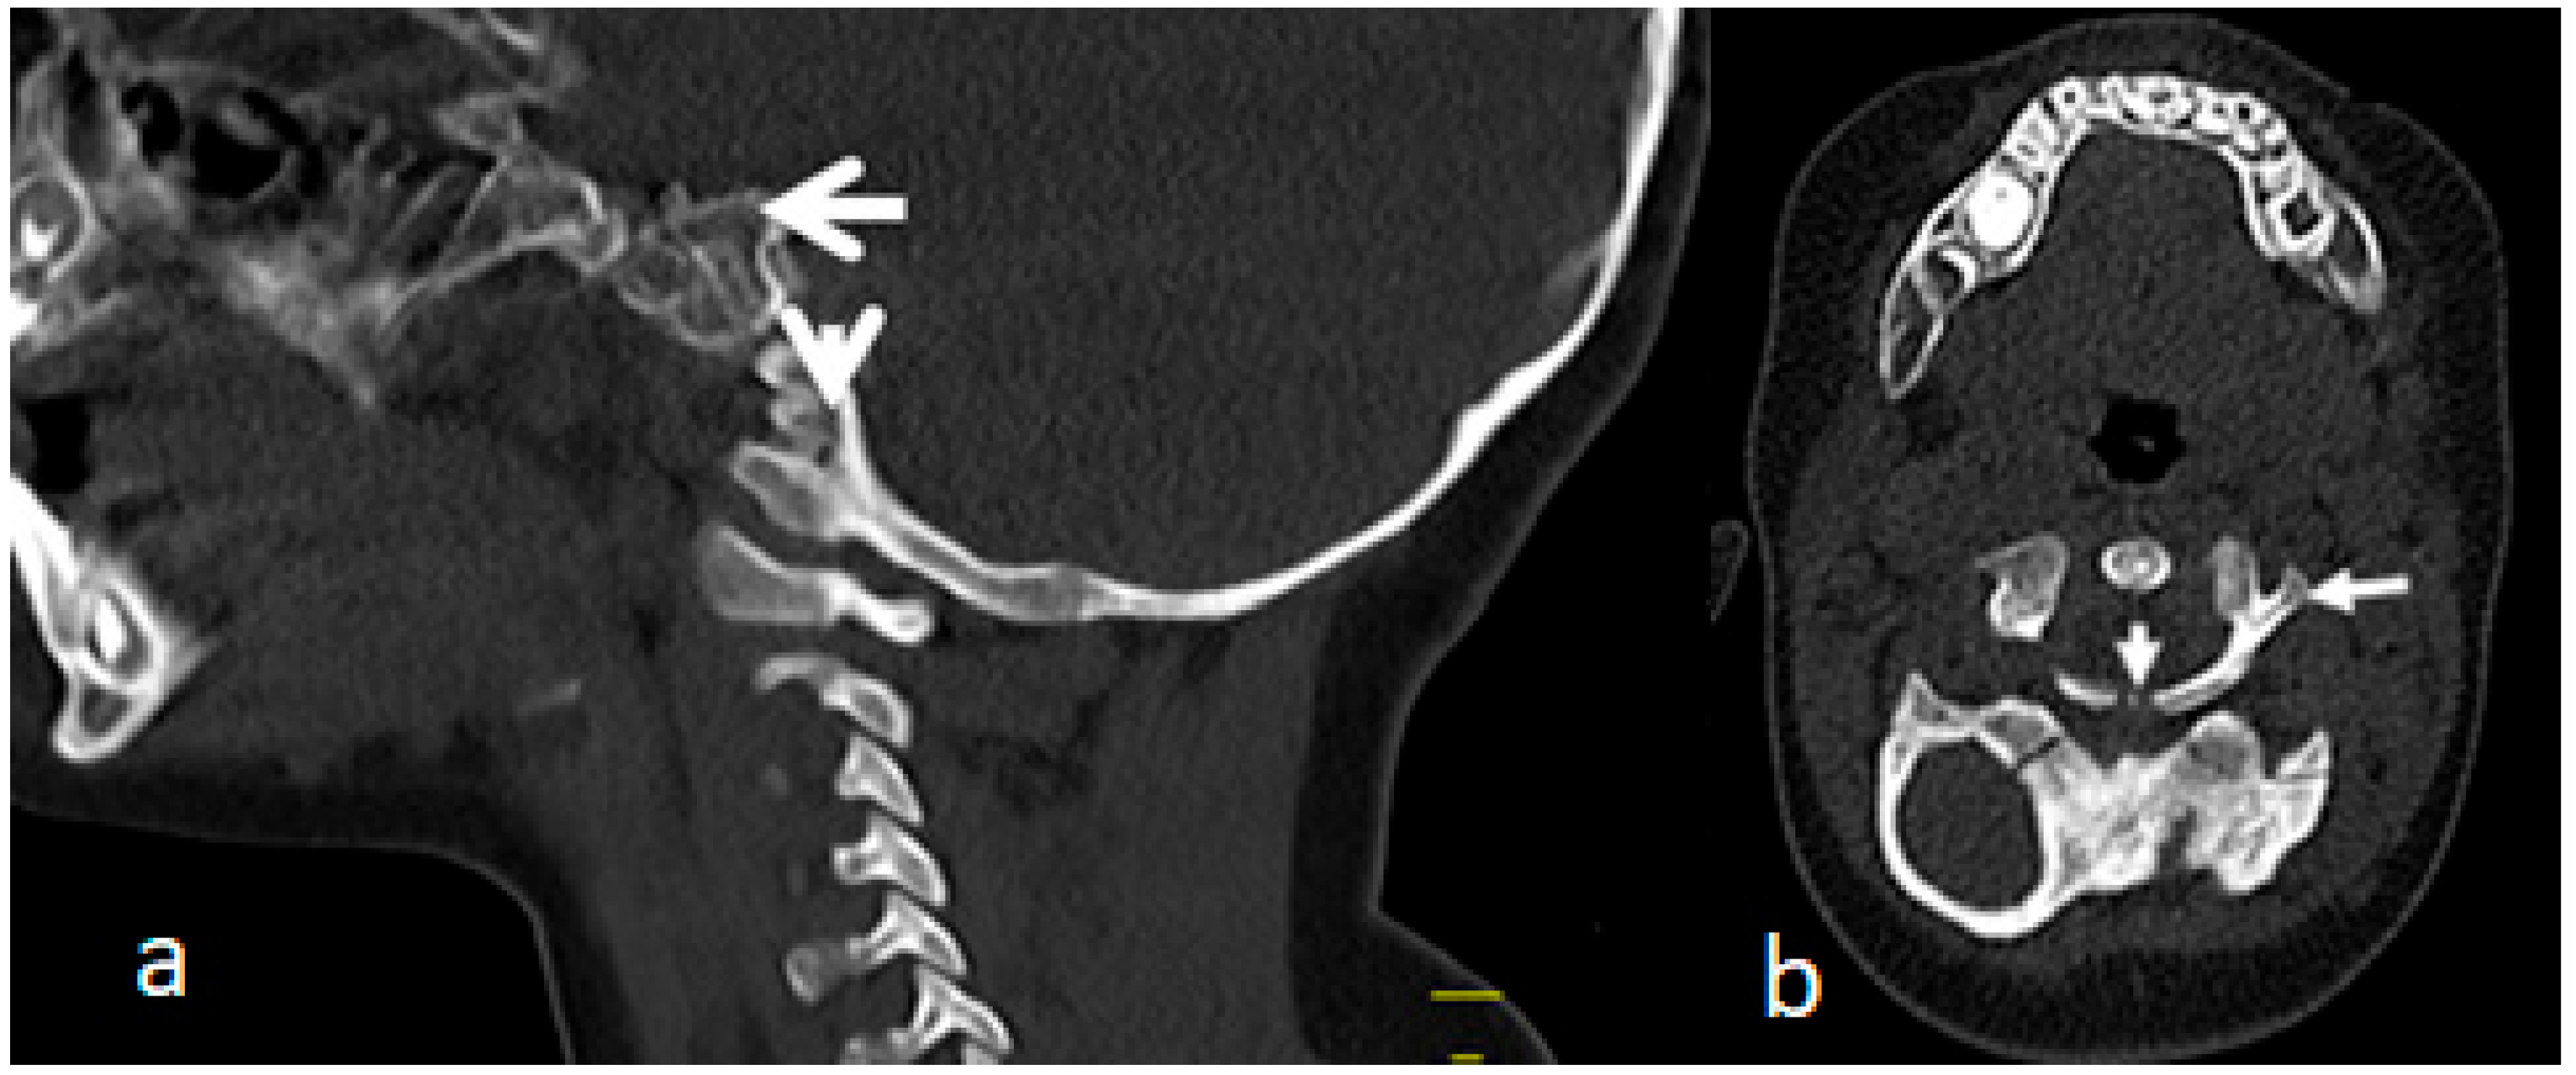

A sagittal cervico-thoracic MRI of a 2-year-old boy with Larsen syndrome showed cervico-thoracic kyphosis (Cobb’s angle of 90°) (Figure 5a). A sagittal cervico-thoracic 3D-reformatted CT scan of a 7-year-old child with Larsen syndrome showed hypoplastic anterior and posterior arches of the atlas fusion of C2-3 and hypoplasia and fragmentation of the seventh cervical spine (arrow) (Figure 5b). A 3D reconstruction CT scan of the same child showed fusion of C2-3 associated with hypoplastic vertebral bodies causing the development of acute cervico-thoracic kyphosis (Figure 5c).

Figure 5.

(a–c): A sagittal cervico-thoracic MRI of a 2-year-old boy with Larsen syndrome showed cervico-thoracic kyphosis (Cobb’s angle of 90°) (a). Sagittal cervico thoracic 3D-reformatted CT scan of a 7-year-old child with Larsen syndrome showed hypoplastic anterior and posterior arch of the atlas associated with fusion of C2-3, hypoplasia and fragmentation of the 7th cervical spine (arrow) (b). A 3D reconstruction CT scan of the same child showed fusion of C2-3 associated with hypoplastic vertebral bodies causing the development of acute cervico-thoracic kyphosis (c).